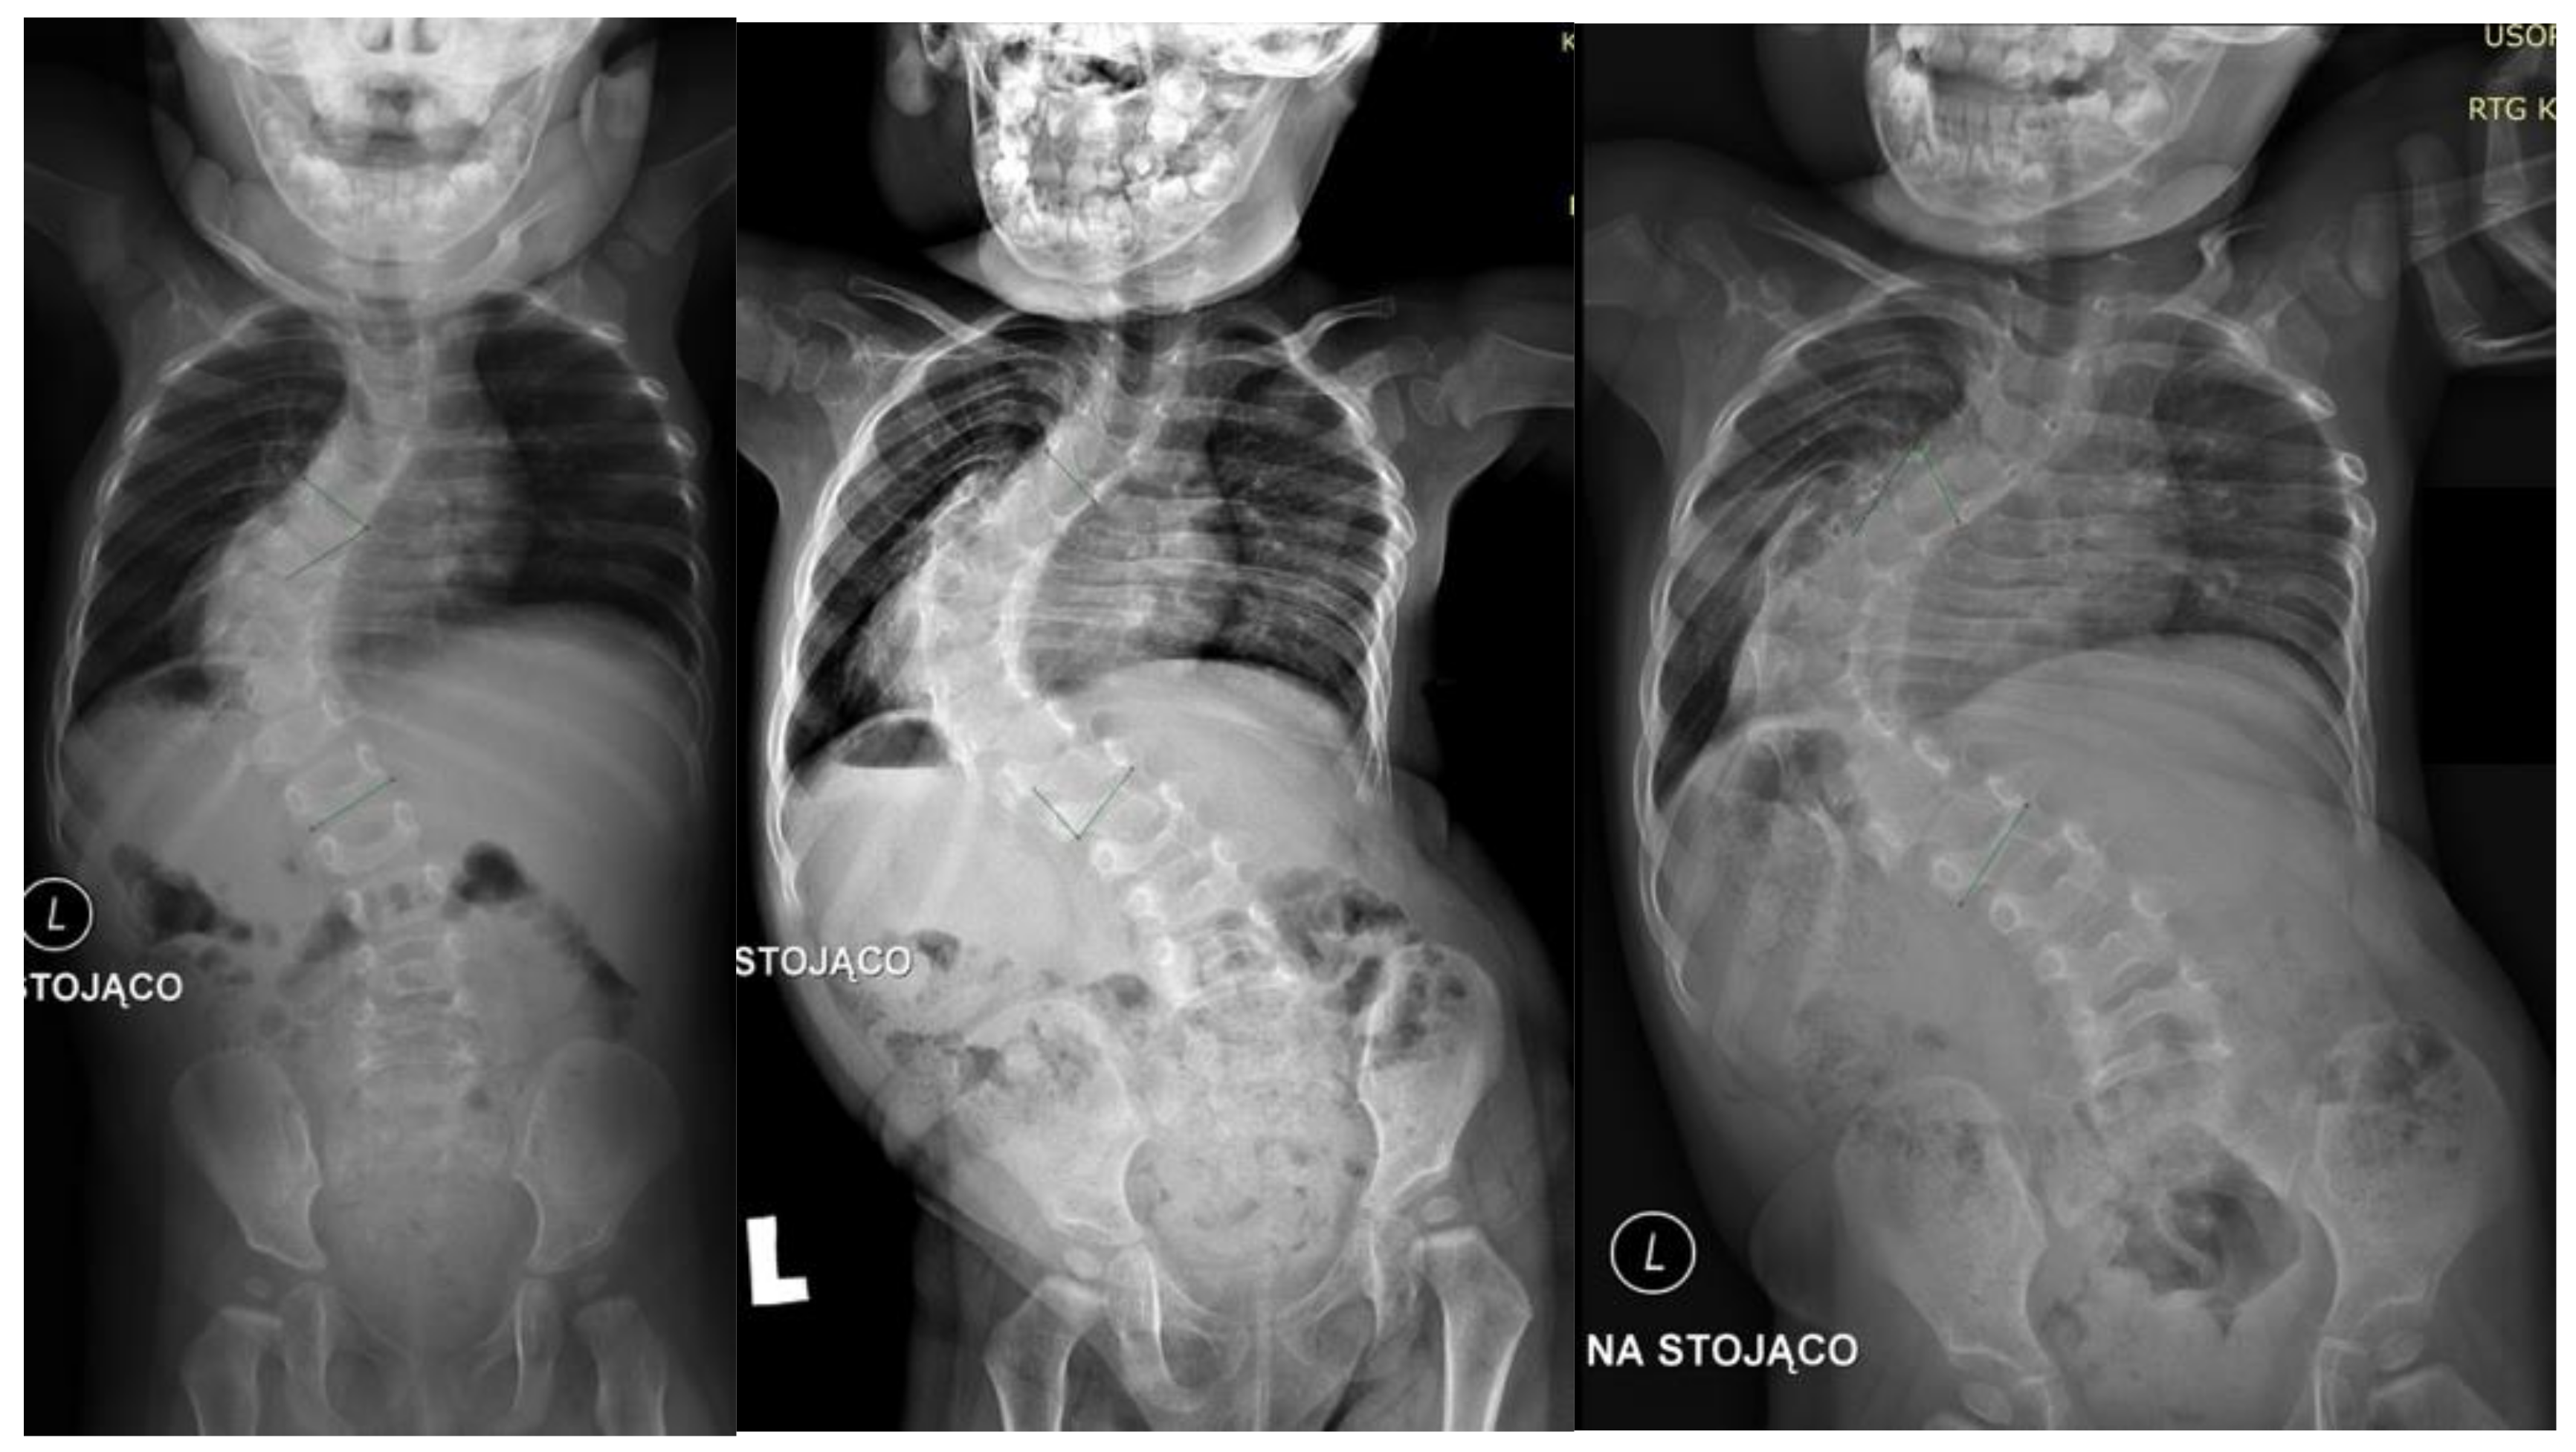

Scoliosis X Ray With Rods Magnetic Growing Rod Scoliosis Early onset scoliosis (eos) presents in patients younger than 10 years. due to these limitations of traditional growing rods (tgrs), the magnetically controlled growing rod (mcgr) system has been developed to allow. After the initial procedure to implant. magnetically controlled growing rods (mcgr) have been gaining popularity in. magec is an evolving magnetically controlled growing rod system. Magnetic Growing Rod Scoliosis.

Scoliosis X Ray With Rods Magnetic Growing Rod Scoliosis Early onset scoliosis (eos) presents in patients younger than 10 years. due to these limitations of traditional growing rods (tgrs), the magnetically controlled growing rod (mcgr) system has been developed to allow. After the initial procedure to implant. magec is an evolving magnetically controlled growing rod system for the treatment of eos. magec growing rods are a. Magnetic Growing Rod Scoliosis.

Scoliosis X Ray With Rods Magnetic Growing Rod Scoliosis magnetically controlled growing rods (mcgr) have been gaining popularity in. After the initial procedure to implant. Early onset scoliosis (eos) presents in patients younger than 10 years. magec growing rods are a new surgical treatment for children with severe spinal deformities that uses implantable rods and. due to these limitations of traditional growing rods (tgrs), the magnetically. Magnetic Growing Rod Scoliosis.